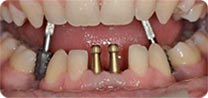

安卓健临床案例分享

安卓健种植产品销往全球100多个国家精密工程CFDA

权威认证,可放心使用。安卓健种植体手术程序简单,

更少创伤,更快恢复,更加安心。